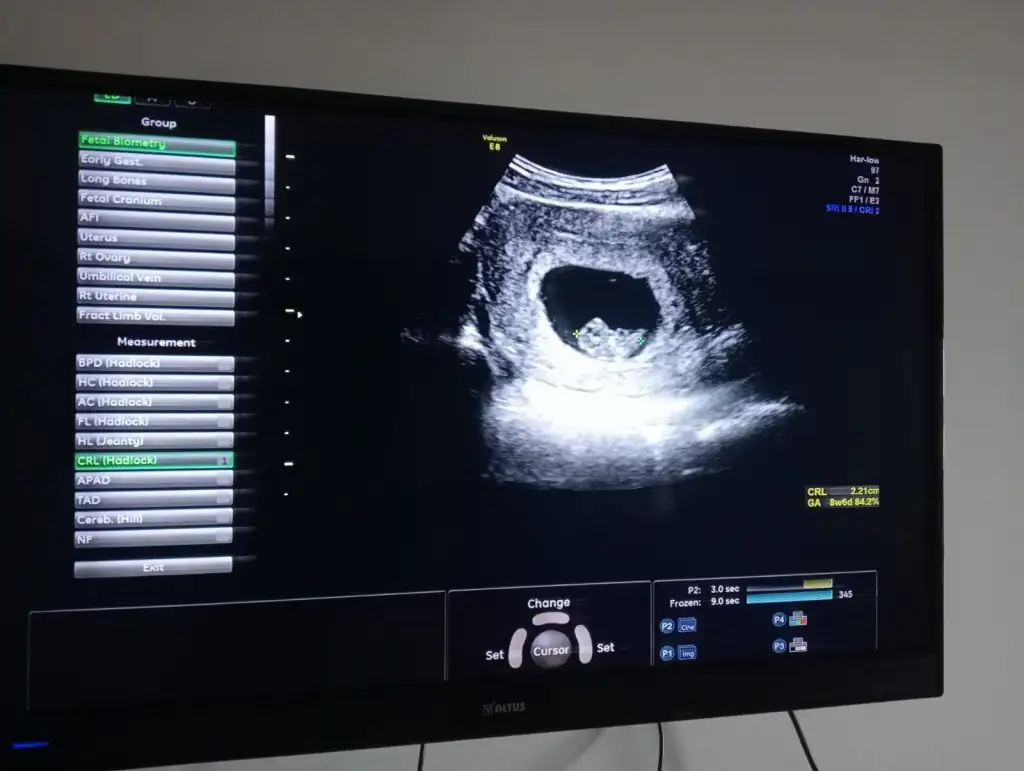

Kızlar 6+6 karından ultrason yorumlarmısınız 🌸🙏

Eklentiler

• IMG_20230419_115656.webp

IMG_20230419_115656.webp

17,8 KB · Görüntüleme: 92